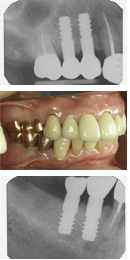

またAQB新聞No.16(2007年7月版)の3頁でも紹介したように、AQBの残存率は母集団1500本(植立間もないものから18年半までのもの)で、96~97%で、3~4%は抜去や脱落があることになる。

その再植立の料金であるが、一応補償期間は10年と考えているので、例えば5年後に再植立の場合には5割引、3年後に再植立なら7割引、8年後に再植立なら2割引でそれぞれ植立している。

また、上部構造もそれに準じた割引を実施している。1ピースAQBユーザーの中でも中位から安めの料金設定と思われるが、これでも歯科医院の経営が成り立っているわけであるから、ほぼ妥当な料金なのだと思う。

しかし、これは2ピースではなく1ピースAQBであるからこそ成せる業なのだと思う。このように廉価の設定ができるということは1ピースAQBの大きな優位性といえるのではなかろうか。結び